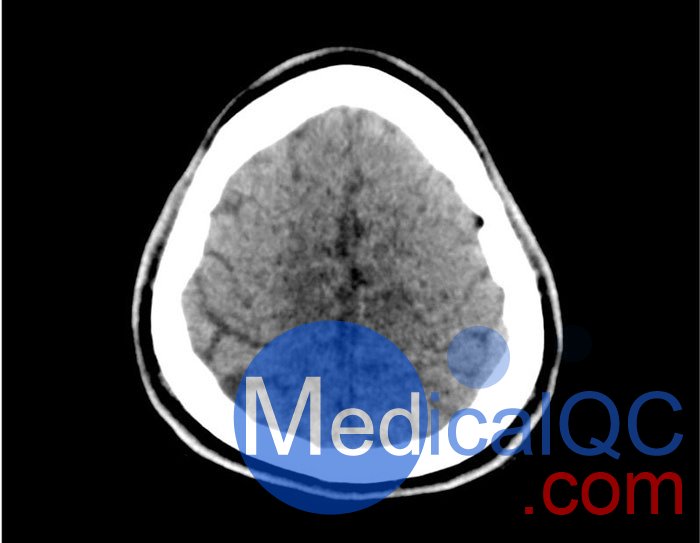

50-01頭部CT模體,50-01腦中風(fēng)頭部模體,50-01腦出血頭部模體模擬了具有中風(fēng)和出血模式的頭部。它覆蓋枕骨大孔的頂點(diǎn)。

卒中模式包括早期梗死的體征(大腦中動(dòng)脈高密度、基底神經(jīng)節(jié)消失)、急性和亞急性分水嶺梗死以及不同年齡的腔隙性梗死。

出血模式包括蛛網(wǎng)膜下腔出血、不同年齡的硬膜下出血、腦室內(nèi)出血和腦出血。

50-01頭部CT模體,50-01腦中風(fēng)頭部模體,50-01腦出血頭部模體影像效果圖: